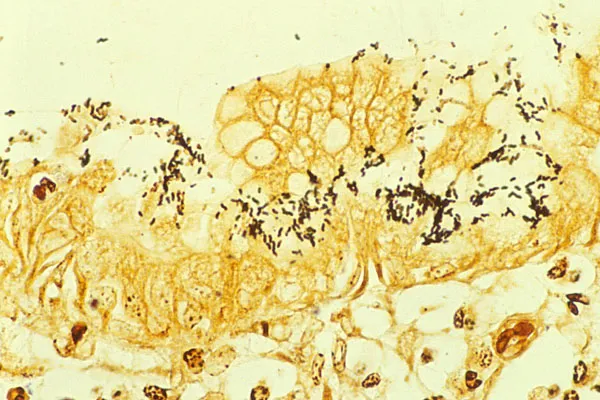

H. pylori - The Spiral Bandit

- Gram-negative, spiral-shaped bacterium primarily colonizing the gastric antrum.

- Urease: Neutralizes gastric acid by converting urea to ammonia, allowing survival.